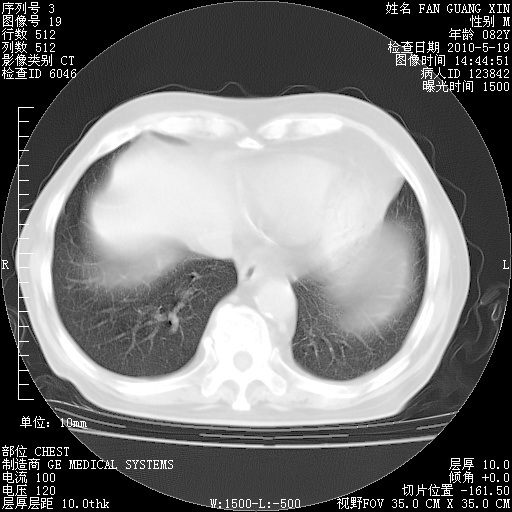

复查肺部CT,明显好转。为什么发热呢?

治疗3周后的肺部CT